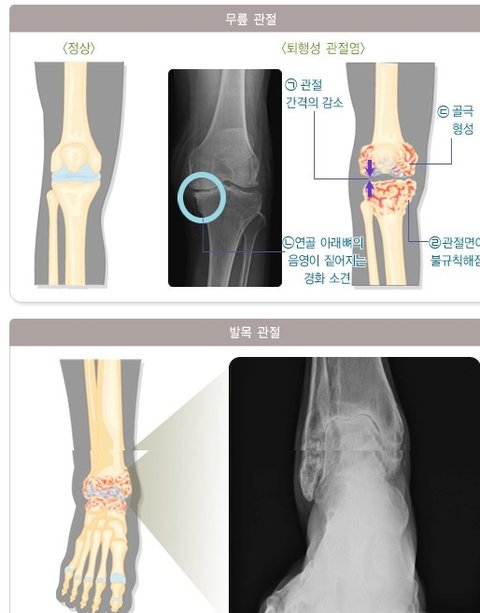

젊고 건강한 신체를 갖는 것은 모든 사람의 바람이다. 최근 서구식 식생활과 편의시설의 증가로 퇴행성관절염 환자가 갈수록 증가하고 있다. 퇴행성관절염은 최근 연구들에 의해 나이가 젊은 사람에게도 흔히 발생한다는 것이 알려지면서 퇴행성관절염이란 말 대신 ‘골관절염’이란 용어를 사용하고 있다.

골관절염은 관절을 이루는 연골에 손상이 생기고 이것이 뼈와 인대에도 진행되면서 염증과 통증이 생기는 질환이다. 관절의 질환 중에서 가장 흔한 것으로 방사선 검가에서는 55세 이상인 경우에는 약80%, 75세인 경우에는 거의 전인구가 이 질환을 가지고 있는 것으로 알려져 있고 이 가운데 4분의1정도에서는 임상적인 증세가 나타난다. 남자보다는 여자에게 더 많이 나타나며 그 정도도 심하다. 또한 비만인 경우, 과거에 교통사고나 외상으로 인하여 뼈나 관절이 다쳤던 경우, 선천성 기형이 있는 경우, 뼈 대사에 이상이 있는 경우, 직업 또는 취미로 한관절을 계속해서 무리하게 사용하는 경우에도 잘 생길 수 있다. 초기에는 약간 동통을 느끼며 춥거나 습기가 많은 날 악화된다. 운동 시 피로를 쉽게 느끼고 관절이 붓거나 움직일 때 뻣뻣하고 관절 주위의 압통을 느끼기도 한다. 장기화 되면 체중 부하가 많은 관절에 심한 운동장애가 나타나고, 관절의 변형으로 인하여 운동할 때 마찰음이 생긴다. 임상적인 경과는 일반적으로 서서히 진행되며 호전과 악화가 반복적으로 나타난다. 그러나 류마티스 관절염과 달리 전신증상은 보이지 않는다. 이 질환이 지속되면 통증과 관절의 변형이 유발되며 손, 발, 척추와 체중부하를 많이 받는 관절, 즉 고관절이나 무릎관절에 잘 발생한다. 특히 무릎의 골관절염은 만성적으로 신체의 장애를 유발하는 가장 흔한 원인이다.